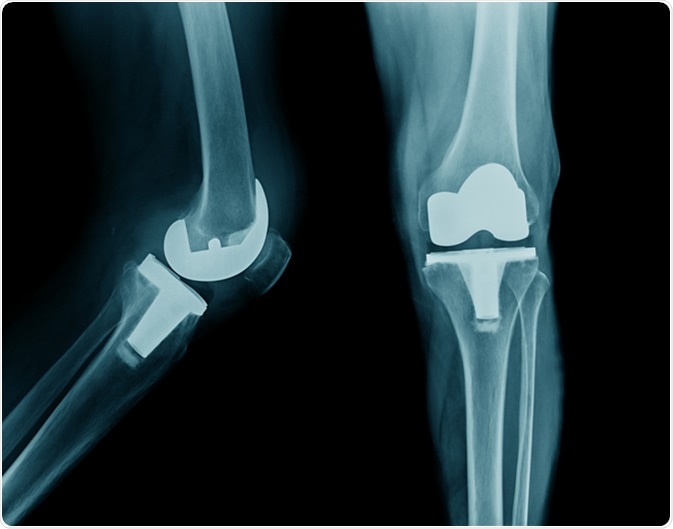

X-ray image total knee arthroplasty. Image credit: Tridsanu Thopet / Shutterstock